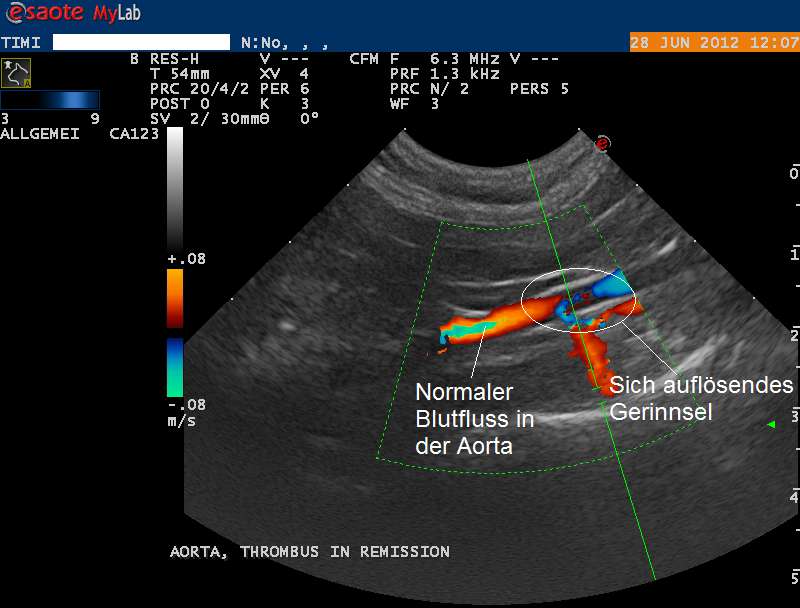

Im Lauf der nächsten Tage verbessert sich der Zustand von Timi zusehends. Der Schenkelpuls ist wieder an beiden Beinen spürbar und die Pfoten erwärmen sich zusehends. Eine weitere Ultraschalluntersuchung zeigt, dass die Körperschlagader in der Region des Verschlusses deutlich besser durchgängig ist.